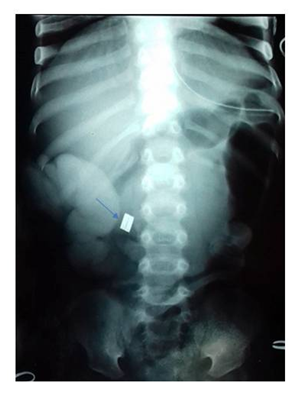

An 18-months-old- child was admitted for febrile occlusion evolving for 48 hours. The physical examination revealed a fever at 38°C, dehydration stage II and a distended with sensitive abdomen. Radiography showed metallic sphere of 5millimetersin the upper abdomen without pneumoperitoneum flank (Figure 1). After conditioning and ressisutation, a transverse laparotomy revealed generalized peritonitis with two perforations of the hail at 600 and 800millimeters from the Treitz angle (Figure 2). It was related to a necrosis of the intestinal wall between two magnets. A peritoneal toilet with a terminal ileostomy was made. The clinical evolution was favorable. Closure of the stoma was performed after one month and follow-up is about 3years.

Figure 1 Radiography: Metallic sphere of 5mm in the upper abdomen with pneumoperitoneum flank.